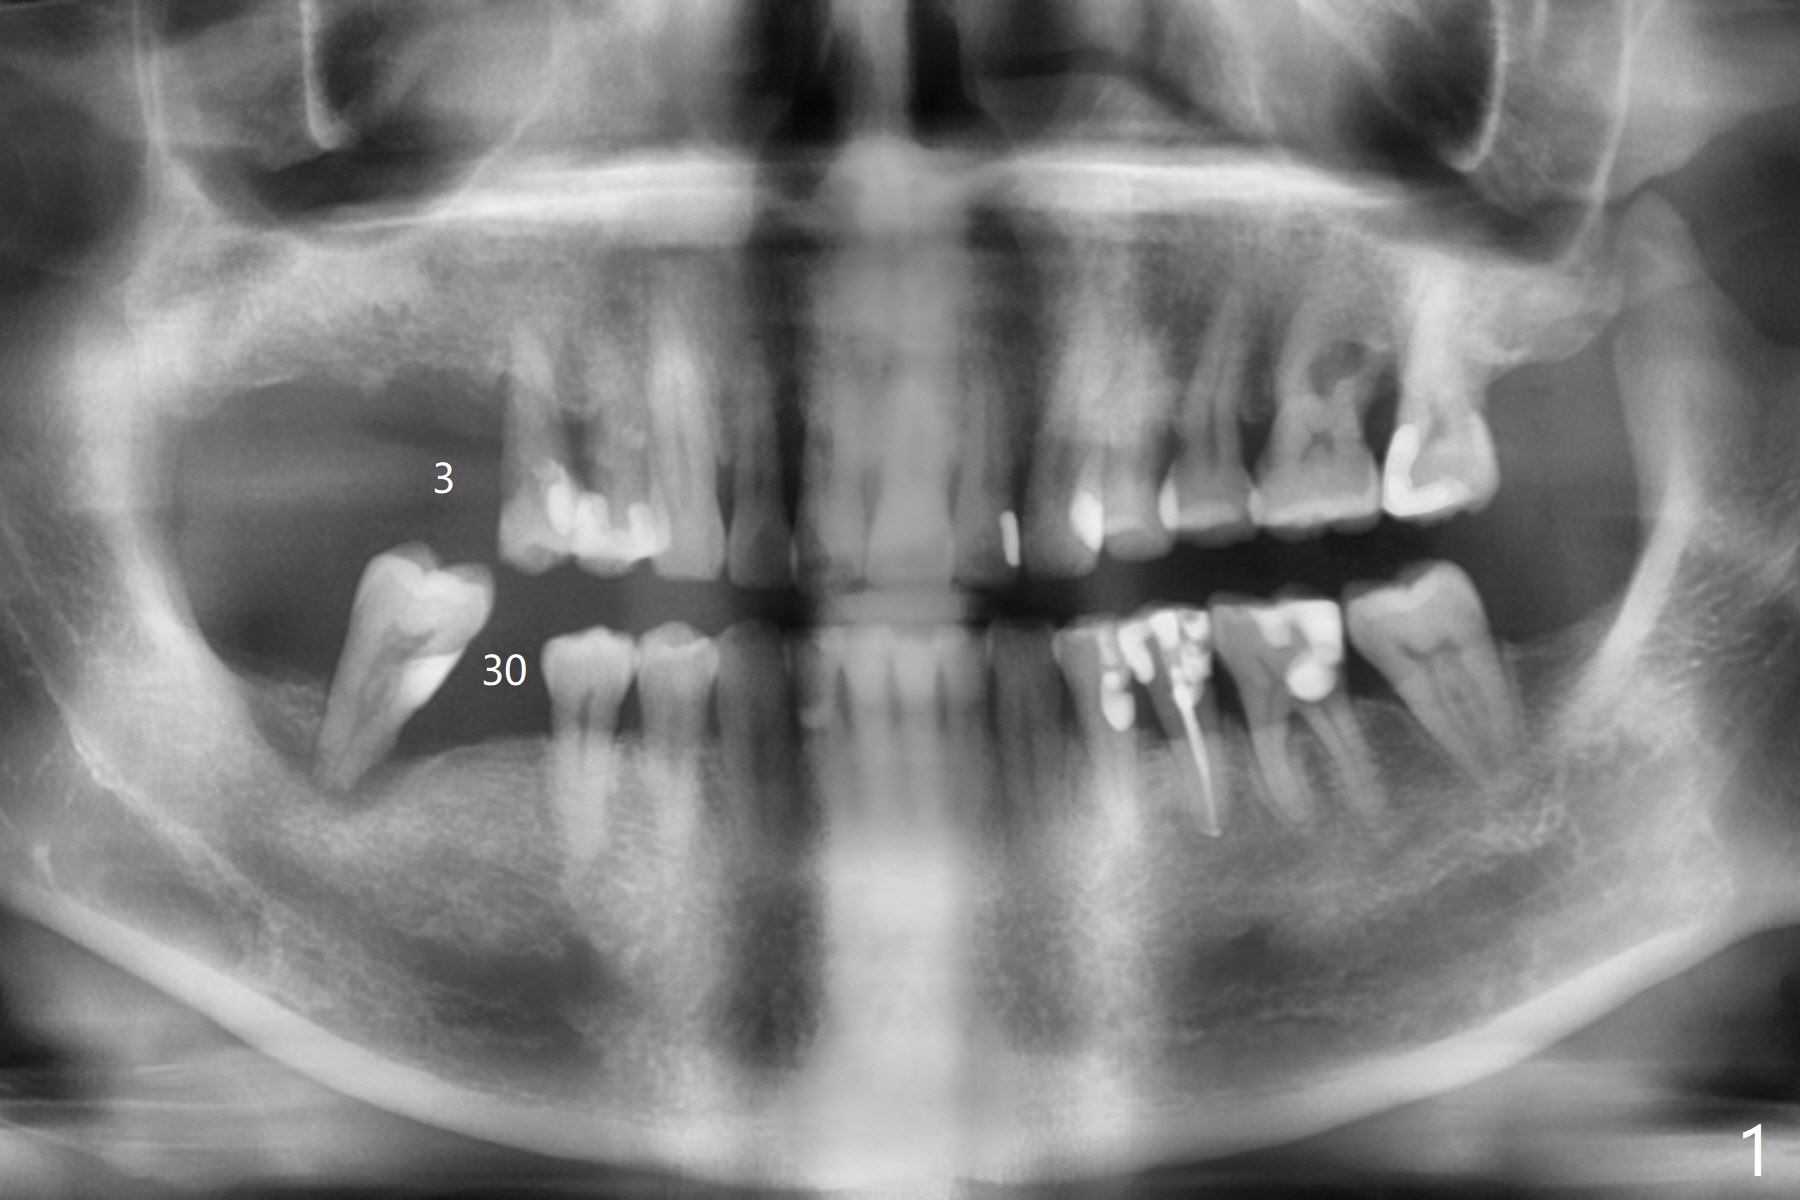

In spite of financial constraint of a 62-year-old man with a dental insurance with limited annual allowance, CT and impression are taken for surgical guides for #3 and 30 at the same time in order to establish a better occlusion over the posterior overjet (Fig.1). The implant at #3 will be placed this calendar year (Fig.2), while the one at #30 early next year (Fig.3). The tooth #31 will be extracted with #30 implant placement. The bone harvested from osteotomy will be mixed with Osteogen and placed in the #31 socket. An immediate provisional at #30 will be extended distal to cover #31 socket. Use Osteogen or Collagen plug if necessary.